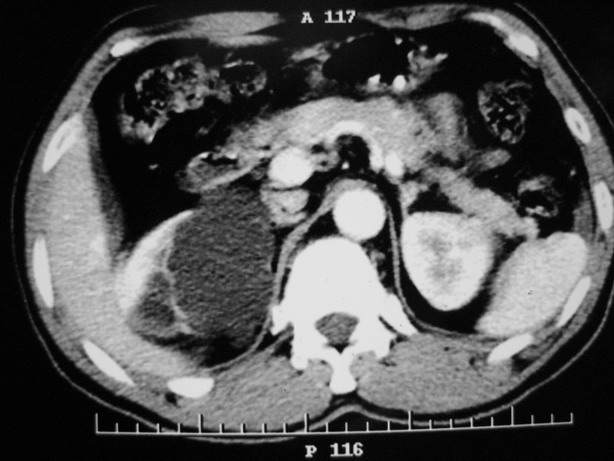

标题: CT10772:男性,48,右肾盂旁多囊性占位! [打印本页]

男性,48,体检发现,平时无症状。

平扫:

肾盂旁多囊性占位,有实性成分,增强有轻度强化,收集期病变内无造影剂显影。诊断肾盂旁囊肿,有实性成分无法解释,查书后诊断为:多房性囊性肾瘤!!不知大家同意否?????????对本病知道不多,望大家不吝赐教!!

右肾多发囊性低密度影,囊内有增强的隔及实性组织,考虑囊性肾癌。